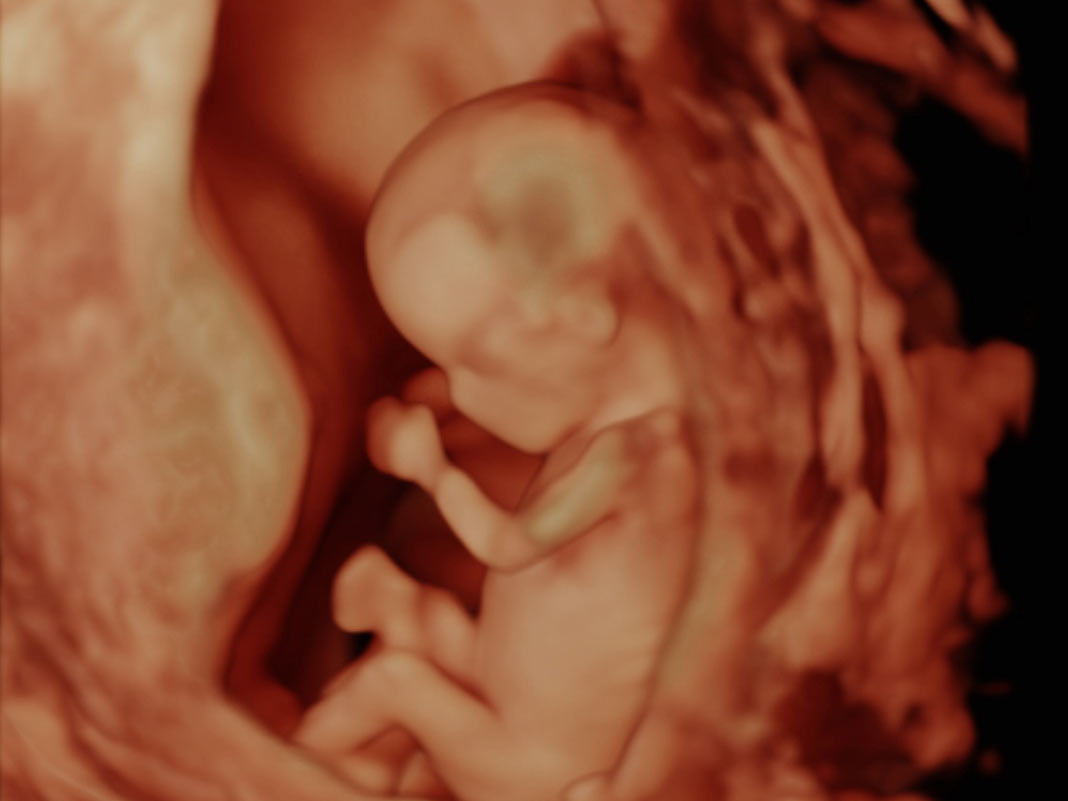

Ersttrimester Ultraschall

Unsere moderen Geräte zeigen Ihr Ungeborenes bereits von seiner besten Seite.

Sehen Sie sich das Video an und überzeugen Sie sich, wie viel Freude die ungefährliche Untersuchung machen kann, aber natürlich auch davon, wieviel man schon sehen kann - sogar als medizinischer Laie.